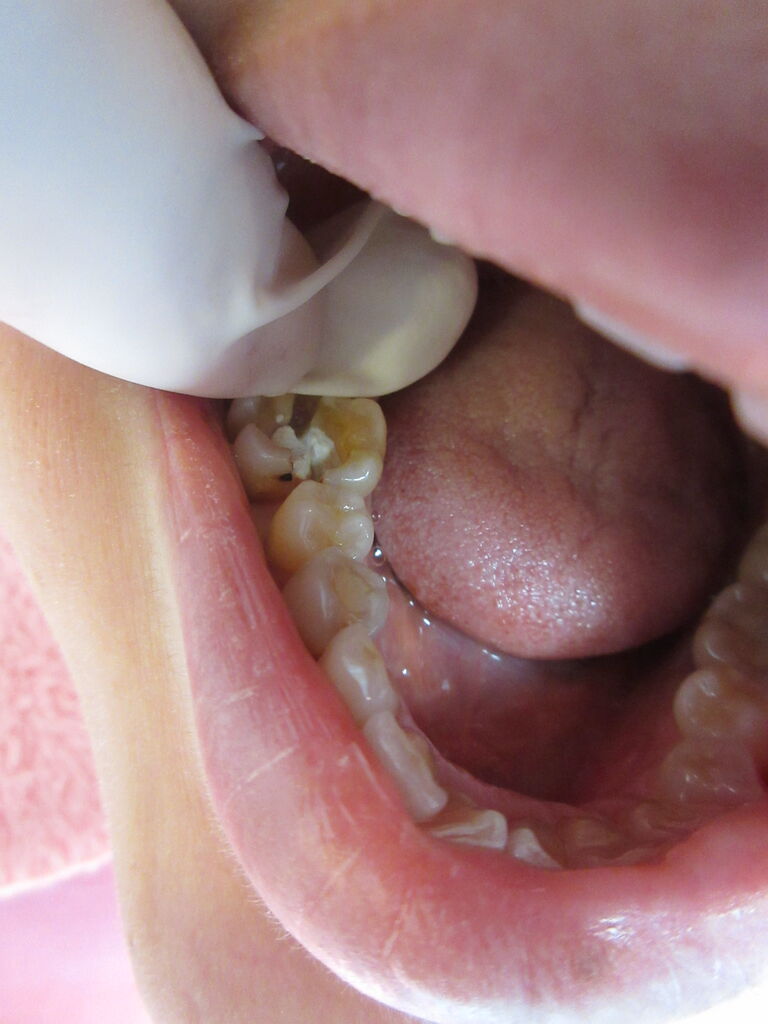

治療しているのに、中断してしまいますと、いろいろなトラブルが出ます。

この患者様は神経を取ったまま、来院せず。

痛みが出たため来院、歯が折れてました。